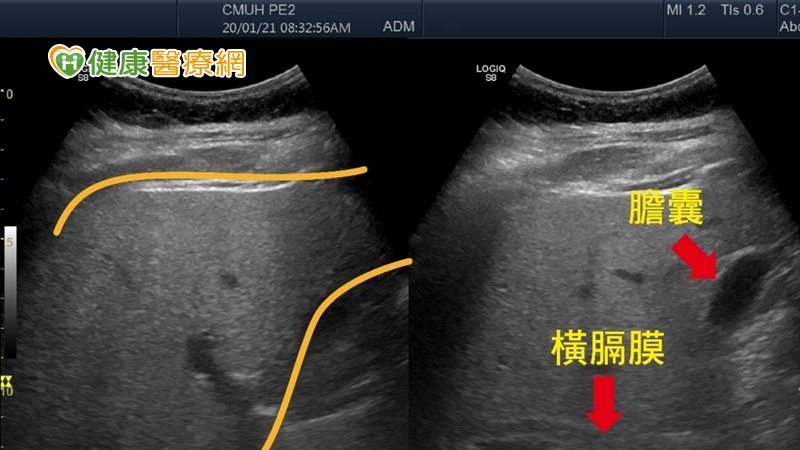

▲2條黃色線內是肝臟的範圍,肝臟因堆積較多脂肪,導致超音波下肝臟是白花花一片,箭頭處為膽囊與橫膈邊界變得模糊,是重度脂肪肝的影像表現。(圖/中國醫藥大學附設醫院提供)